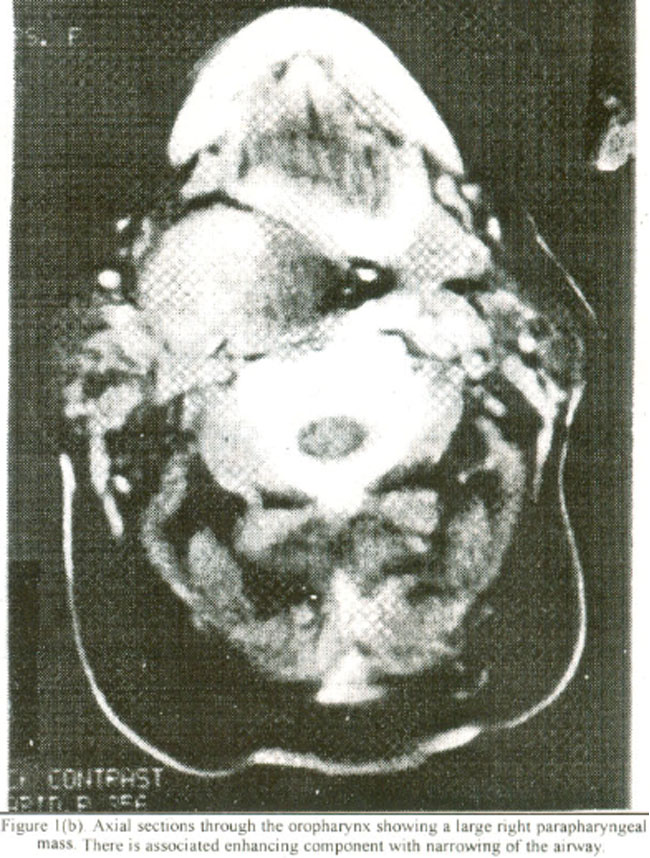

A 52 years old lady presented to the casualty department with a two day history of progressive difficulty in breathing. and a 12 hour history of difficulty in speaking and SW allowing. On examination, she was found to be in distress, inspiratory stridor and a raised respiratory rate. There was slight intercostals recession, but she was not cy anosed. The patient was pyrexial and there was a bulge of the soil palate and the tonsil on the right side, causing obstruction to the airway There was no palpable mass on examination of the neck. Her white cell count was raised. A diagnosis of an obstructive inflammatory mass was made and she was given intravenous steroids and antibiotics. Since her condition did not improve after few hours of observation and due to increasing hypoxia on blood gas analysis, she was taken to operating theatre, and tracheostomy was done under local anaesthesia, which relieved her airway obstruction. A plain arid post contrast CT Scan of the neck (Figure Ia and Ib)

showed a large parapharyngeal mass on right side with significant mass effect. The oropharyngeal airway was significantly compromised. The mass showed an associated area of intense contrast enhancement suggestive of a vascular lesion. Fine needle aspiration cytology under ultrasound guidance confirmed its vascular origin most likely a haemangiocytoma. Because of CT Scan and FNAC reports, carotid angiography was done, which showed mass effect and displacement of carotid vessels without any abnormal vascularity. The tumor was explored via a trans-parotid trans- cervical approach. Facial nerve and its branches were identified and preserved. The tumor was found to be arising from the deep lobe of the parotid gland, which was removed. Histopathology showed the mass to be a pleomorphic adenoma. Following removal of the tumor she made a full and uneventful recovery. A five-year follow-up showed no evidence of recurrence.

Figure 1. Plain (a) and contrast (b) axial sections through the oropharynx showing a large right parapharyngeal mass. There is associated enhancing component with narrowing of the airway.